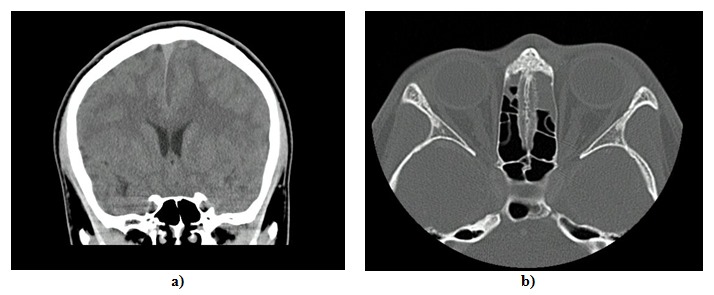

Paralelamente, el paciente fue valorado por pediatría, el servicio tratante, que al encontrarlo con ptosis palpebral, solicitó un TAC de órbitas y de cráneo contrastado (figura 1). Según los hallazgos, se inició un manejo antibiótico con 1,5 g de ampicilina/sulbactam cada 6 h. Posteriormente, se cambió el manejo a vancomicina IV de 500 mg/6 h, 1 g de ceftriaxona cada 12 h y metronidazol IV de 500 mg cada 8 h por parte del servicio de infectología pediátrica, en sospecha de infección del sistema nervioso central; por ello, adicionalmente, se solicitó la toma de una resonancia magnética de cerebro (figura 2). Para este momento, el paciente ya presentaba un puntaje de 10/15 en la escala de coma de Glasgow (GCS) con hemiparesia derecha y persistencia de alteración del estado de conciencia, que en conjunto con hallazgos imagenológicos determinaron la valoración por neurocirugía.